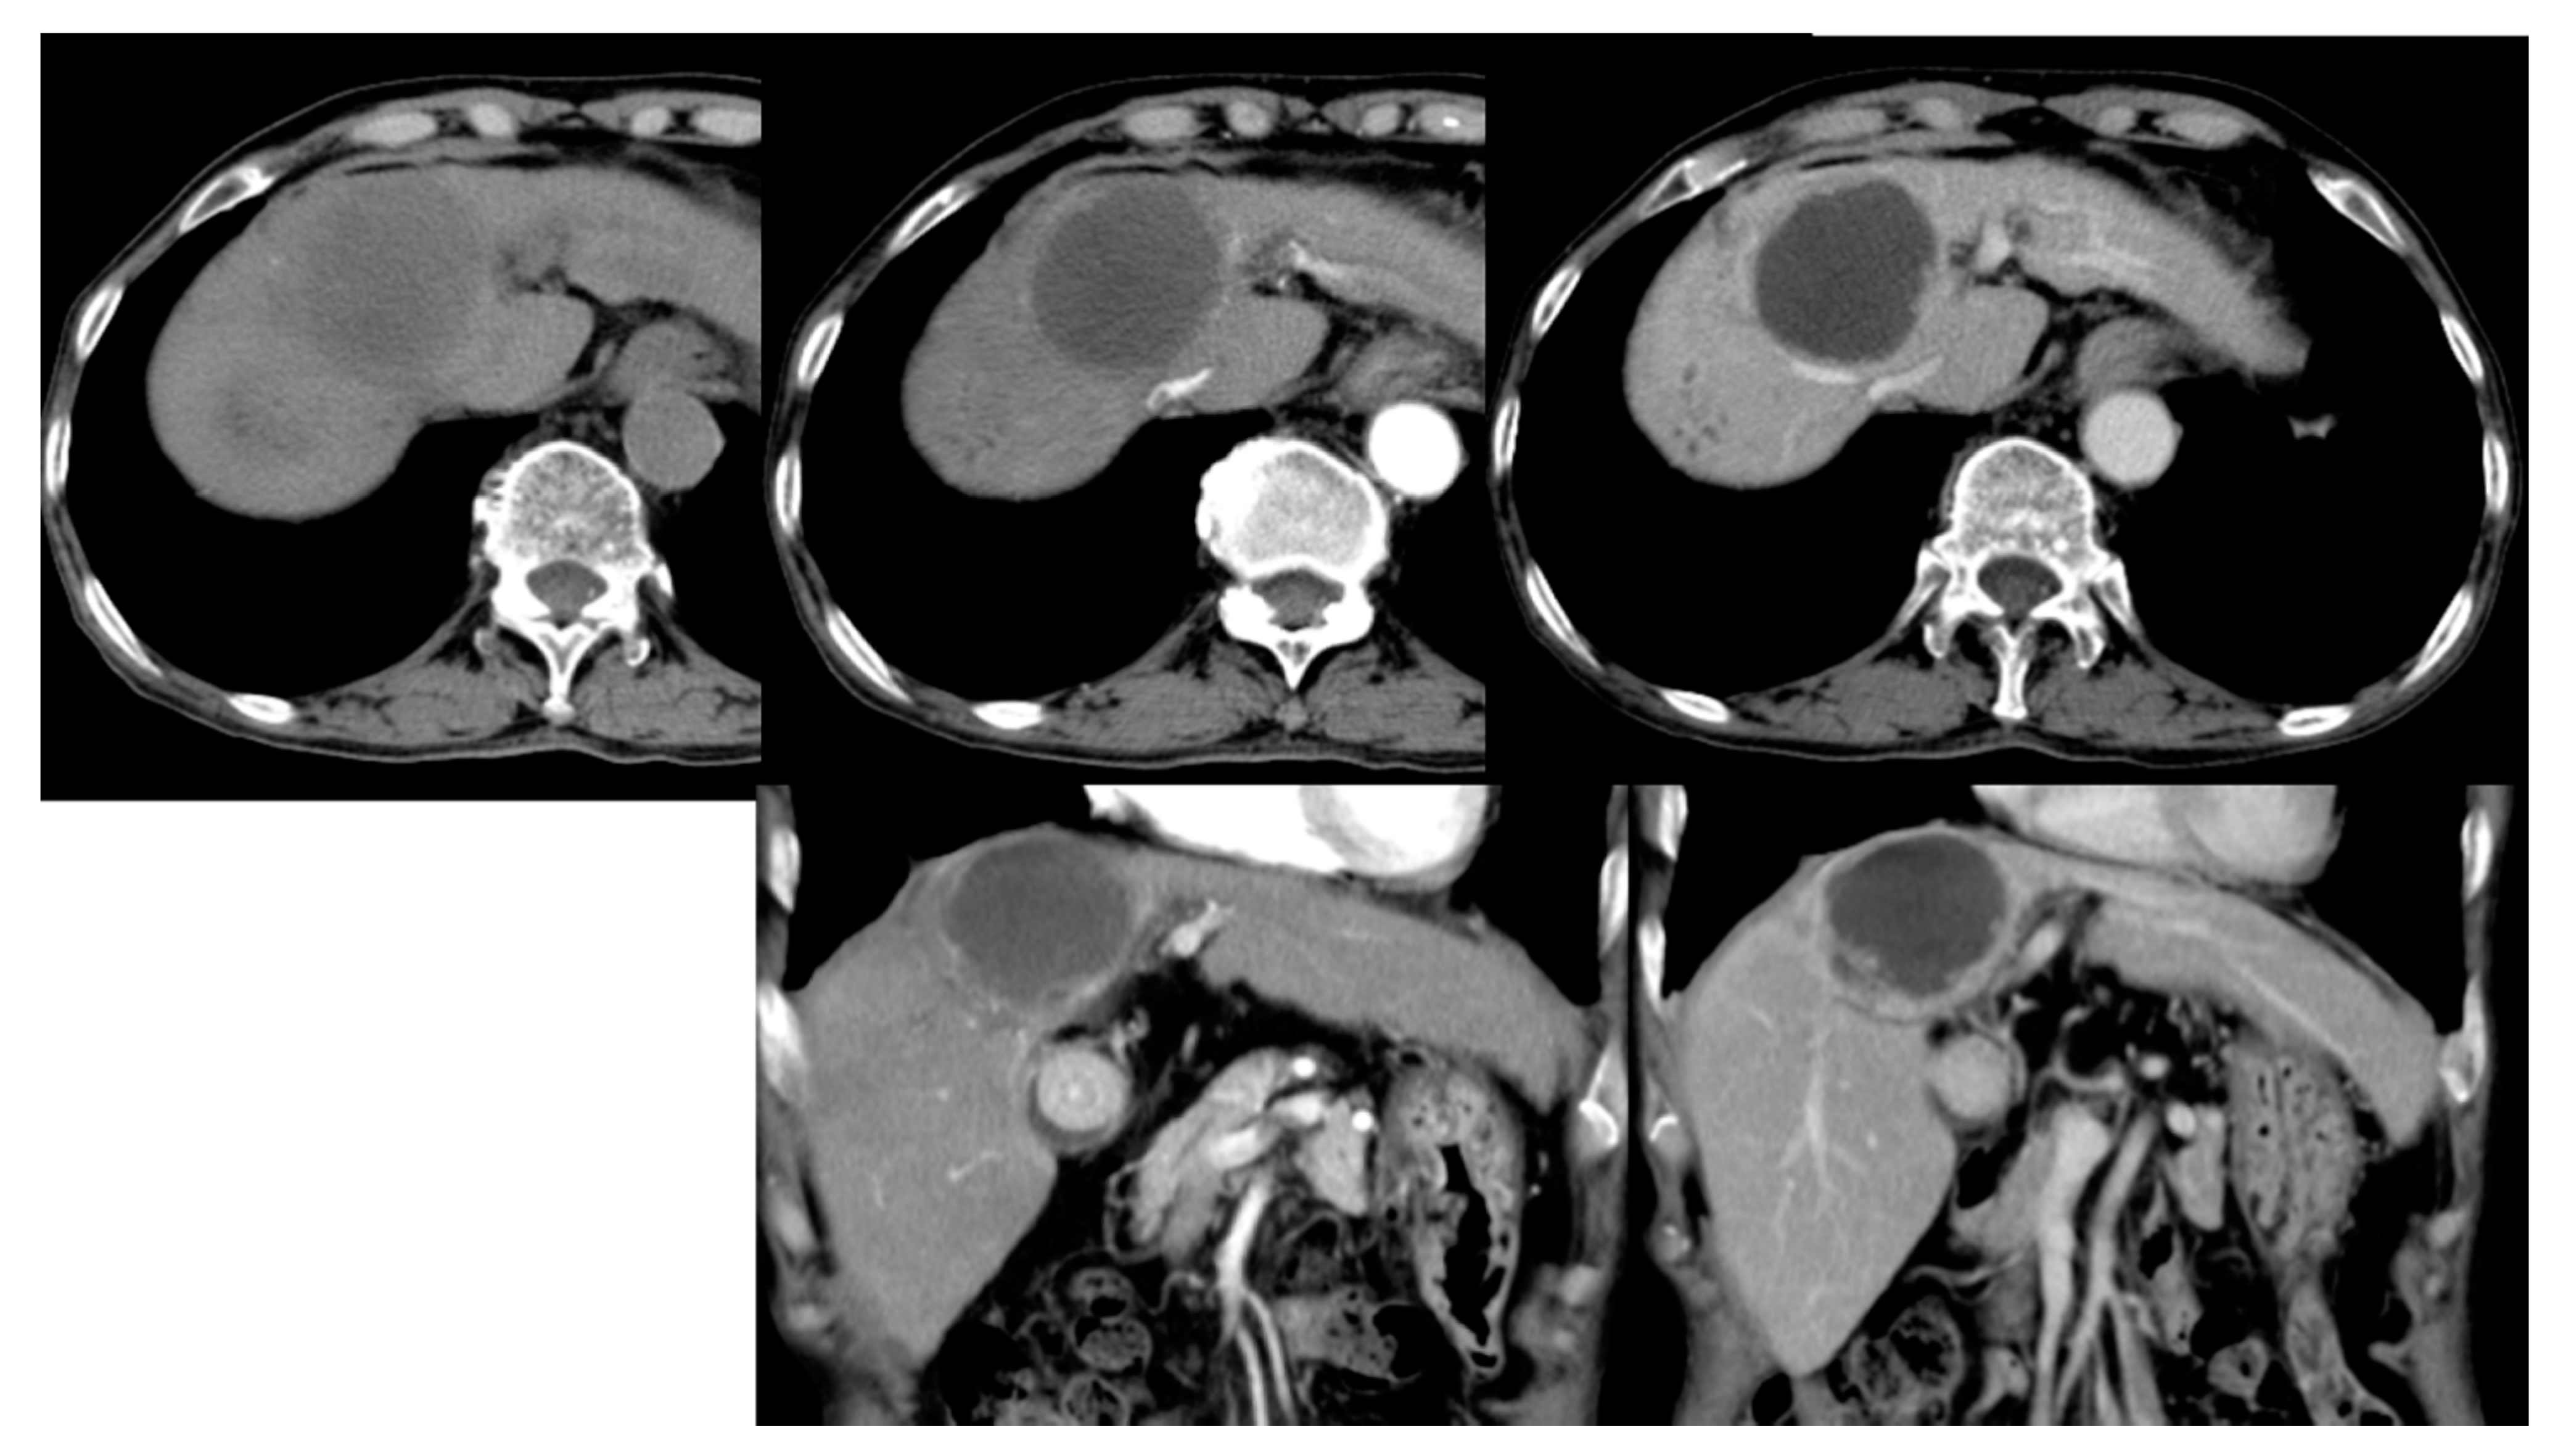

Currently, hepatic artery embolization is performed using two main treatment methods, both involving trans-catheter arterial chemoembolization (“TACE”). Conventional trans-catheter arterial chemoembolization (“cTACE”) is the older of the two methods (Figure 1), whereas microsphere-loaded arterial embolization—called “DC bead TACE”, after the drug-eluting microbeads employed—is the newer (Figure 2). DC bead TACE involves the use of a microsphere-loaded drug that prolongs effective treatment times and results in better therapeutic outcomes [2]. Compared with cTACE, DC bead TACE results in better therapeutic response and delayed tumor progression; however, no significant difference has been noted in liver-related toxicity. Song et al. demonstrated the superior performance of arterial embolization performed using DC beads [3], and Ashrafi et al. indicated that DC bead TACE can result in the same tumor response as cTACE [4]. Although the latter study combined the clinical effectiveness of DC beads with that of cTACE, additional large-scale randomized controlled trials are still needed.

Figure 2.

Microsphere embolization (DC bead TACE). A 7.3 cm hepatocellular carcinoma (HCC) with arterial enhancement in segment 4 and 8 of the liver in both angiography (A, white arrows) and CT (C, * star) images. TACE is performed by using drug eluting microspheres (D and E). Follow-up angiography shows complete embolization of the tumor (B).

Next, only the data of the 61 patients who were treated for single-tumor HCC with DC bead TACE using either 100–300 μm or 300–500 μm microspheres were analyzed to determine the effect of microsphere size on treatment effectiveness. The data were divided into two different microsphere sizes (30 records for 100–300 μm and 31 records for 300–500 μm, as per Figure 2), for a total of 61 records. The result of the chi-square test is shown in Table 6. For microspheres that were 100–300 μm in size, the invalid ratio was 20% and the effective ratio was 80%. For microspheres that were 300–500 μm in size, the invalid ratio was 58.1%, whereas the effective ratio was 41.9%; the chi-square test result was 0.02, indicating a significant difference, that is, microspheres sized 100–300 μm were more therapeutically effective than those sized 300–500 μm in size for a single tumor. The extent of the differences in effectiveness should be further explored.